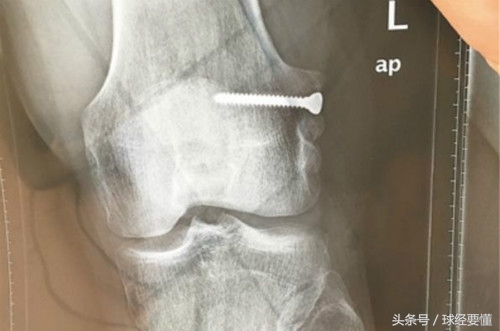

任鹏是来自足球城大连的球员,2013年呼和浩特东进加盟深足。在任鹏17岁那年,因为左膝韧带撕裂,大连铁路医院医生取了一段他的肌腱,用钢钉作为支点,固定在骨头里促进生长,才让他没有离开足球。

13年后,任鹏近日在深圳一家医院,取出了那颗陪伴他13年的钢钉,“17岁的时候医生说我基本可以告别足球了,当时我不愿放弃,命运也不能让我跪地求饶。很幸运我熬过来了,现在我决定把钢钉拿出来,也是为了继续追逐自己的梦想,我相信我还能踢。”

之所以要取出这颗钢钉,是因为前段时间任鹏参加一场预备队比赛,撞伤了左腿膝盖,需要进行核磁共振检查。然而,由于这颗钢钉在骨头里,核磁共振就没法进行了。经过医院诊治,任鹏决定先把钢钉取出来,以便于膝盖的进一步治疗。